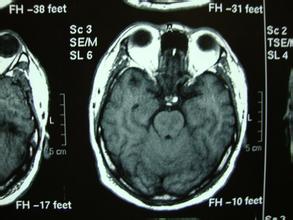

脑干病变;一侧眼睑下垂,瞳孔散大,另一侧上下肢麻木、无力,这很可能是脑干病变,儿童觉于脑干肿瘤,老人则多为脑干血管病,核磁共振可确诊。